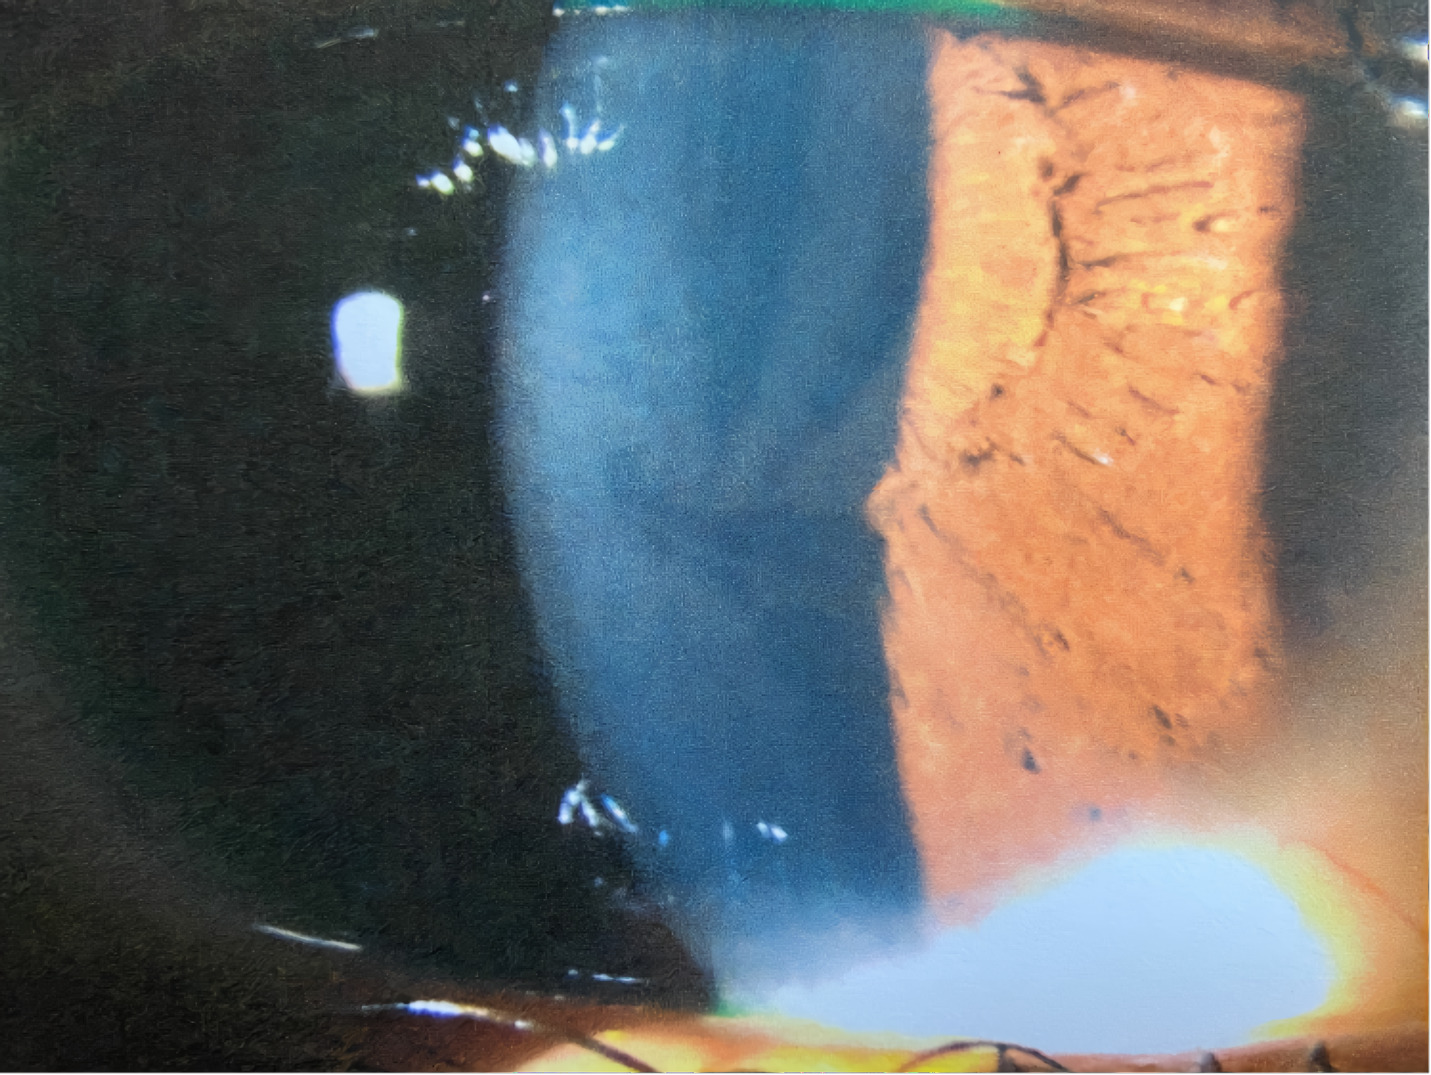

A 21-year-old African American woman presented at Navy bootcamp with complaints of a sudden-onset black spot in her right eye that occurred immediately after vomiting earlier that day. Aside from a complaint of acute gastrointestinal pain, the patient’s medical history was unremarkable. Visual acuity was 20/20 in each eye. Confrontation visual fields were full to finger counting in both eyes. Extraocular muscle and pupil testing were unremarkable. Slit lamp biomicroscopy was remarkable for diffuse brownish corneal epithelial deposits with a central whorl-like pattern in both eyes (Figure 1). Intraocular pressures were right eye 13 mm Hg and left eye 12 mm Hg by noncontact tonometry. Dilated fundus evaluation was remarkable for vessel tortuosity in both eyes and a small vitreous hemorrhage inferior-nasal to the optic disc in the right eye (Figure 2). Posterior segment findings of the optic nerve, macula, and periphery were otherwise normal in both eyes.

Corneal verticillata affects the corneal epithelium and basement membrane, excluding stromal and endothelial involvement.2 This finding is the most common ocular manifestation of Fabry disease, affecting up to 88% of female and 95% of male patients.3,10 It often occurs bilaterally, symmetrically, and with a vortex pattern of pigmented subepithelial or intraepithelial globotriaosylceramide deposits that are taken up by the lysosomes of limbal epithelial cells that differentiate and migrate centrally, forming a whorl pattern.4 A fundamental optical property of the cornea is transparency; however, verticillata neither affects visual acuity nor causes visual symptoms.2